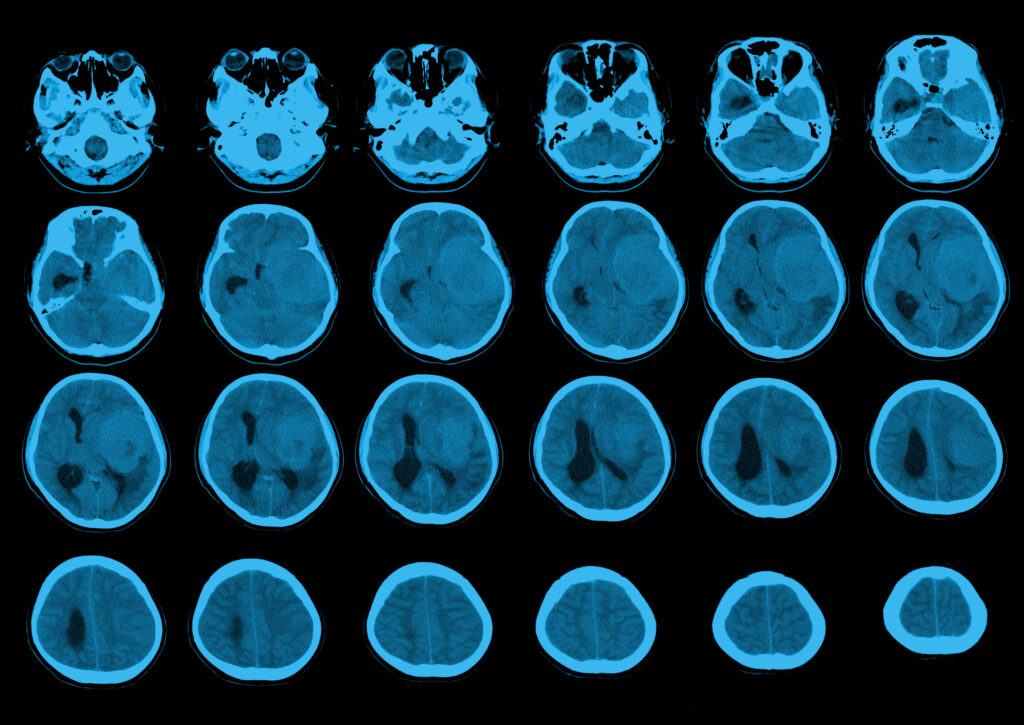

FDA: Depo-Provera Labels Must Warn of Meningioma Risk December 22, 2025 No Comments … Read More Federal Court Creates New MDL for Ozempic and Other GLP-1 Drugs Linked to Vision Loss (NAION) December 17, 2025 No Comments … Read More New Study Links Depo-Provera to Higher Risk of Brain Tumor October 6, 2025 No Comments … Read More